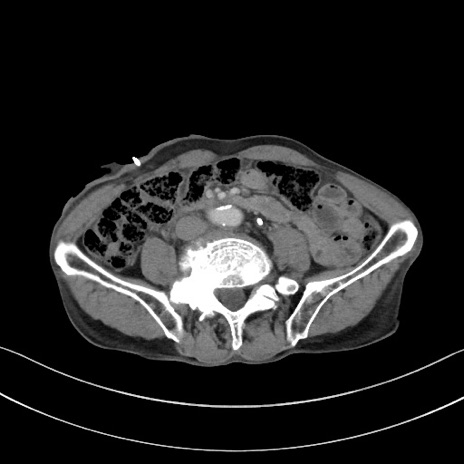

冠状断像

【症例】 70歳代男性

【主訴】右鼠径部腫瘤、疼痛

【現病歴】本日朝より上記主訴あり、受診。

【既往歴】膀胱癌にて膀胱全摘、両側尿管皮膚瘻

【データ】WBC 5600、CRP 0.56